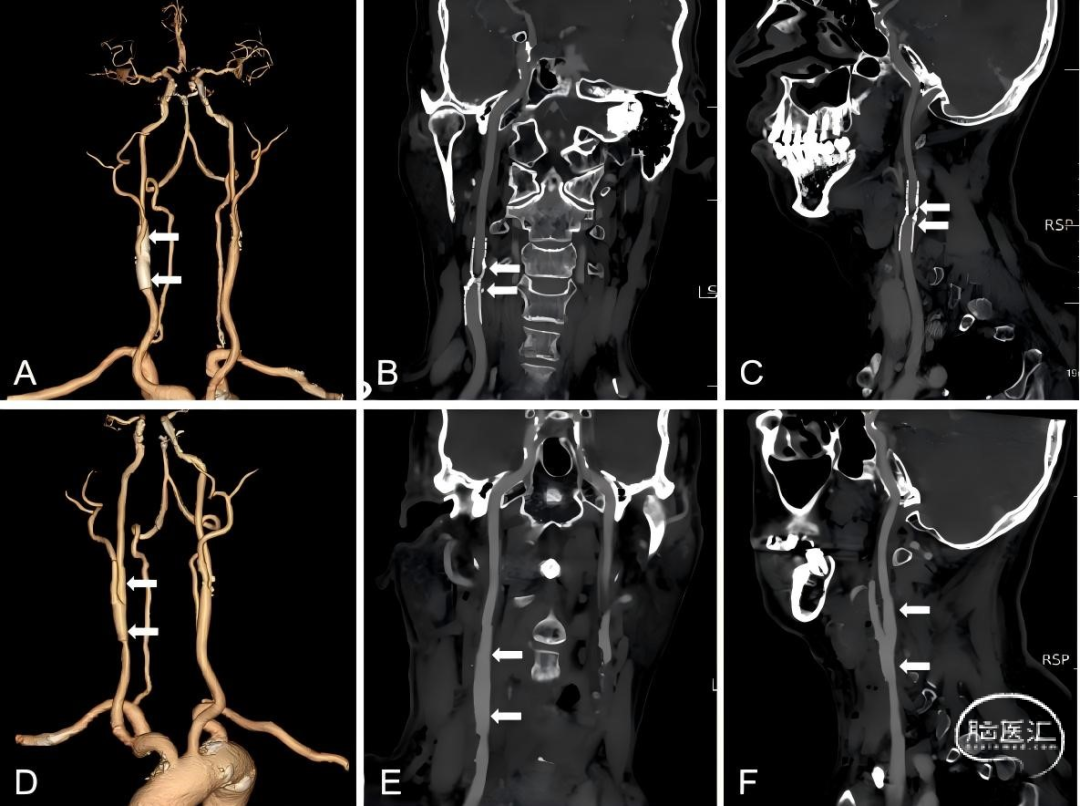

69岁男性,2022年5月因左手无力麻木就诊另一家医院,予以脑血管造影及右侧颈动脉支架植入术。2024年5月因反复头晕再次就诊我院,行头颈联合CTA及超声显示右侧颈内动脉支架内再狭窄,狭窄率73%。予以颈动脉内膜切除术和支架取出术。术后复查颈部CTA显示血流通畅,狭窄被解除。(图1)

图1. 第一次CEA手术前后的CTA。(A)CEA术前CTA的三维结构图,白色箭头指向支架位置。(B-C)CTA冠状位和矢状位显示了右侧颈动脉术前的支架内再狭窄形成(白箭头)。(D)CEA联合支架移除术后CTA的三维结构图,白色箭头指向支架被移除位置。(E-F)CTA冠状位和矢状位显示了再狭窄被解除(白箭头)。